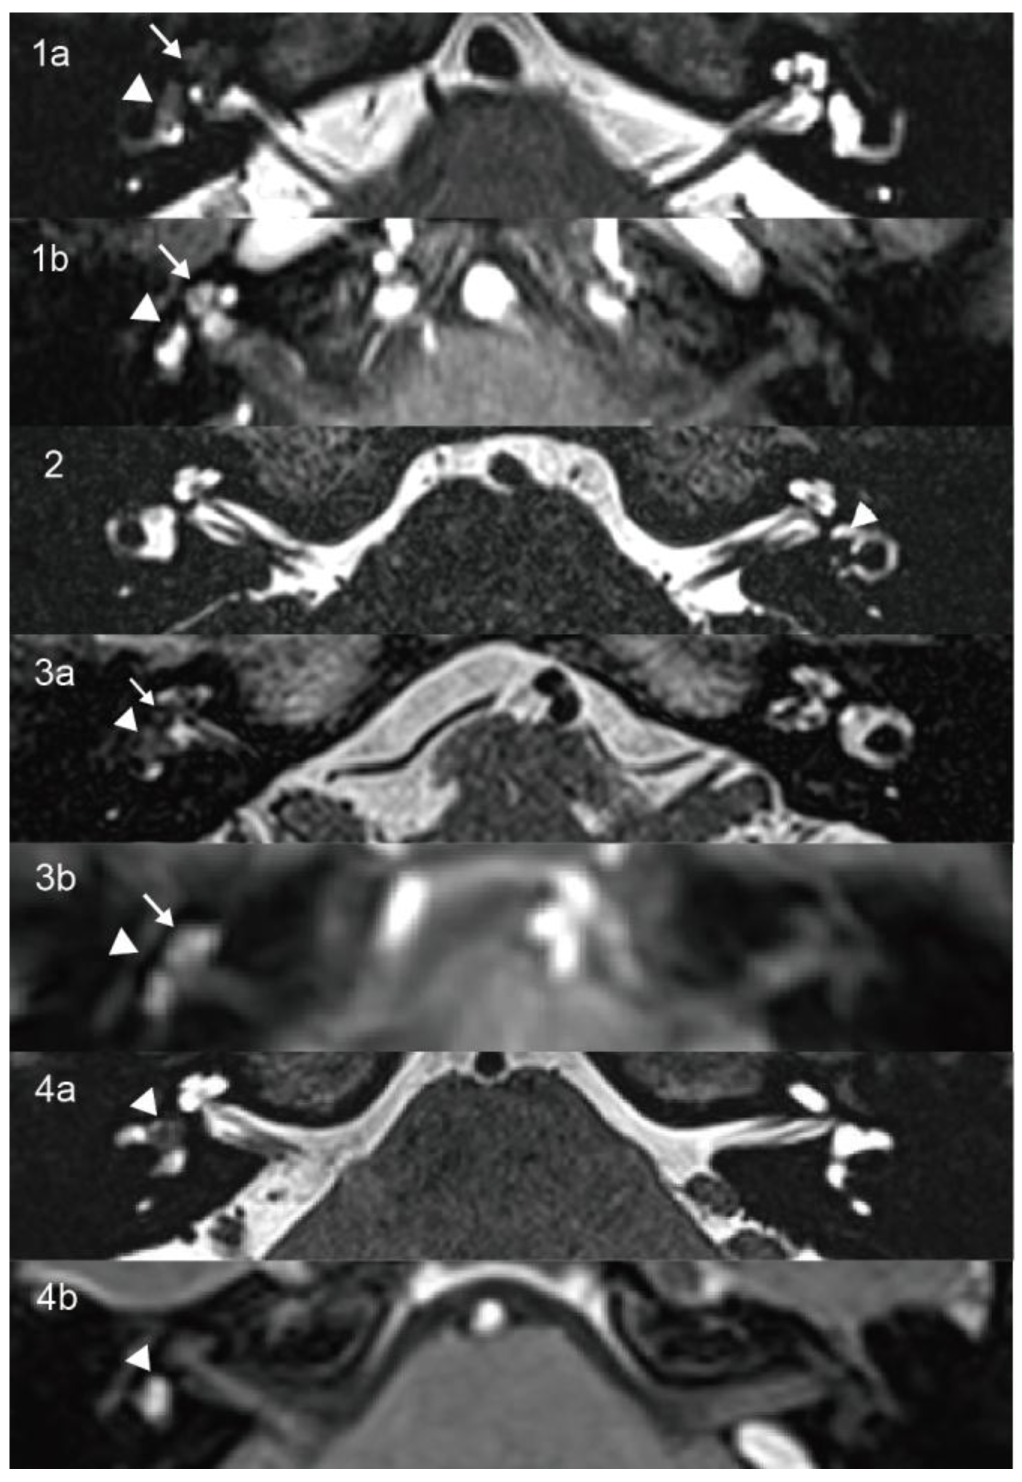

3.1.1. Case 1

| 1 | 60 | F | Recurrent vertigo, tinnitus, HL | Right 3.6 mm | Intravestibulocochlear | >95 | PSNHL | Decreased right mean VOR gain and CSs (0.4/0.74/0.35) | CP = 84% right side hypofunction | NP | NP |